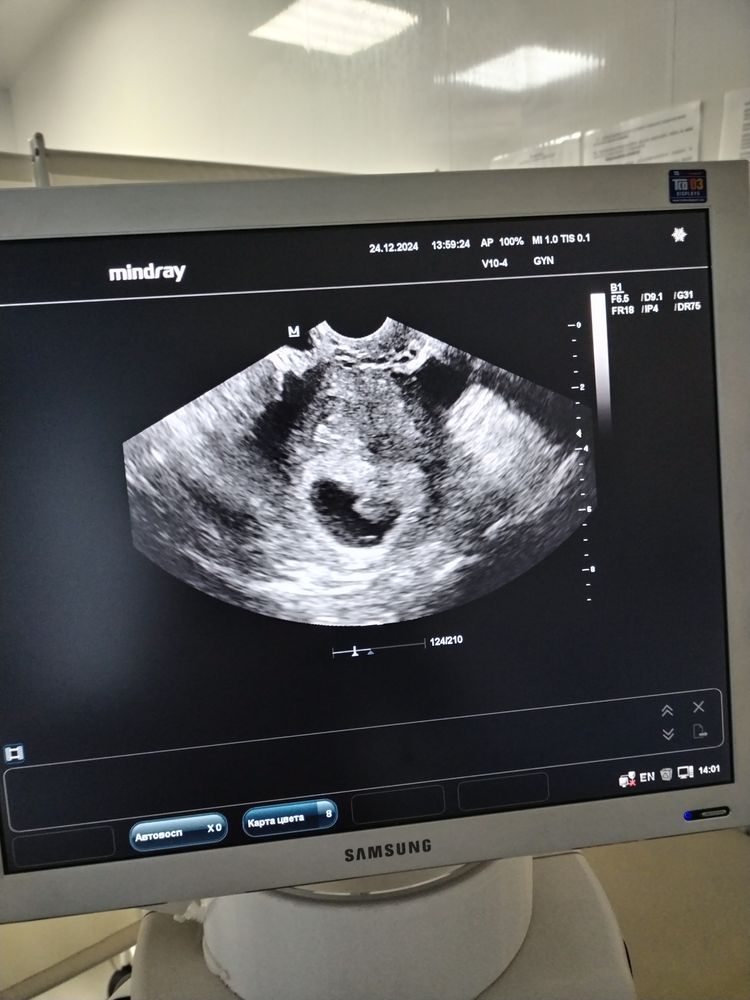

38 ДПП, 8 недель УЗИ

Изображение

У малыша все хорошо. Он уже 16 мм. ЖМ 4,7. Послушала СБ и чуть не расплакалась от милоты❤️